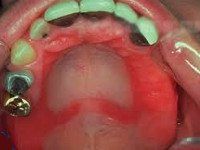

При осмотре полости рта выявляются явления гиперемии, отека, сухости слизистых оболочек, наличие петехиальных кровоизлияний, следы отпечатков зубов на слизистой щек и боковых поверхностях языка. При развитии аллергии к металлическим протезным материалам можно обнаружить нарушение целостности мостовидного протеза, особенно в месте пайки, наличие окисных пленок. Контактный аллергический стоматит, возникший после установки пластмассовых съемных зубных протезов, кроме вышеуказанных признаков характеризуется появлением на слизистой оболочке протезного ложа папилломатозных разрастаний.